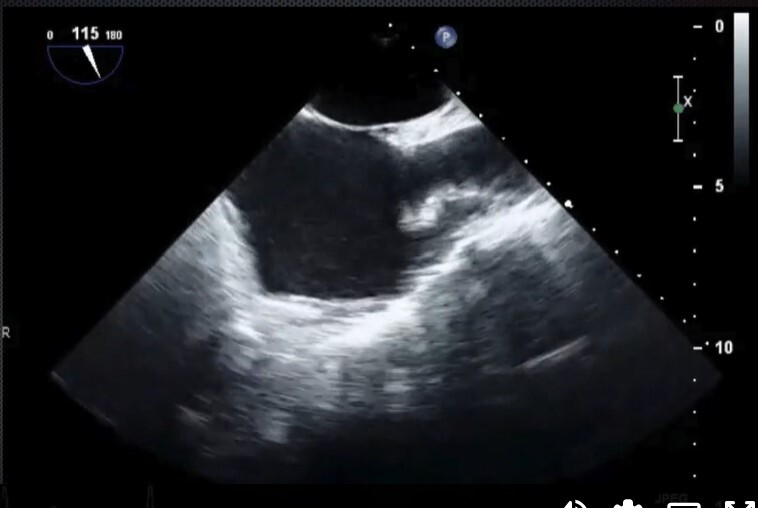

Mid-Esophageal Long Axis View. Multiplane to between 120-140 degrees. Center LVOT. Structures: L atrium, L ventricle, LVOT, aortic valve, R ventricle, posterior & anterior leaflets of mitral valve.